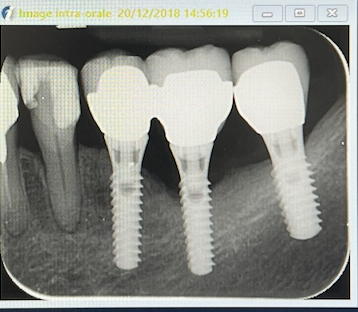

radio le 2O/12/2018

Examen radiologique: alvéolyse horizontale et perte osseuse au niveau de l'implant 36.